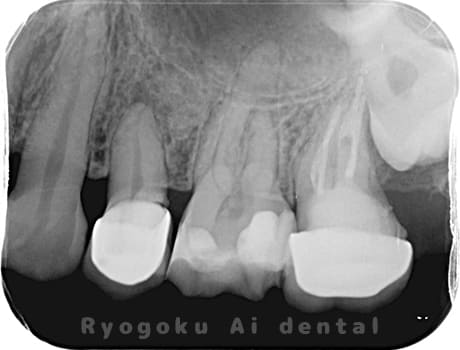

Case02

-

- 原因

- 慢性根尖性歯周炎

- 治療期間

- 3ヶ月

- 治療内容

- マイクロエンド

- 治療費用

- 121,000円

噛むと痛みが出る、とのことで来院した患者様です。他院での根管治療を終えてましたが、根尖病変を認めるため、マイクロエンドを行いました。